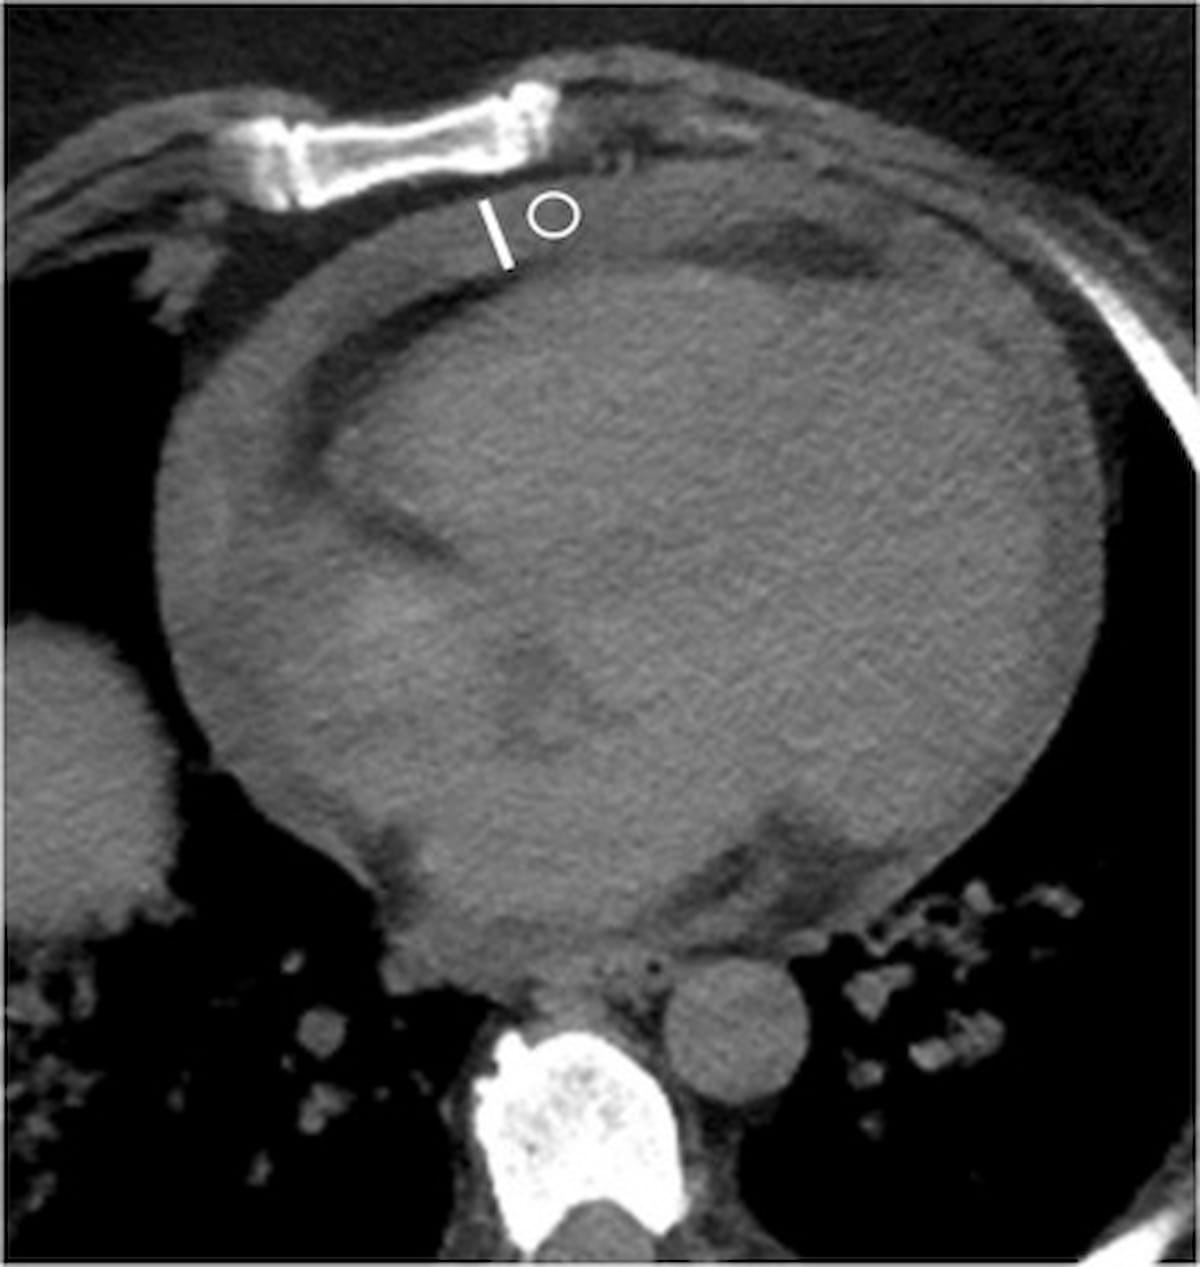

The use of automated detection of large vessel occlusion on computed tomography (CT) through artificial intelligence (AI) software reportedly led to an 11.2-minute reduction in triage time from the completion of imaging to initiation of endovascular therapy, according to newly published research.